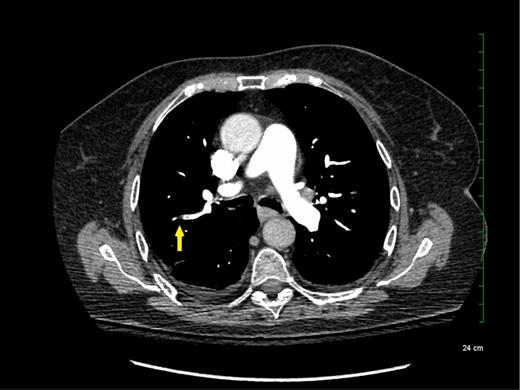

The reported increased incidence of PE diagnosis since the introduction of multirow detector CTPA seems to be correlated with an increase in the diagnosis of PE localized in the subsegmental pulmonary arteries without involvement in larger-order vessels (eg, segmental pulmonary arteries) (see Figure 1). A systematic review and meta-analysis of the literature reported that the rate of SSPE diagnosis among patients who underwent single-row detector CTPA was 4.7% compared with 9.4% for those who underwent multirow detector CTPA.6 Interestingly, the rate of SSPE diagnosis also seems to be increasing with the number of detectors used for PE diagnosis. These rates are reported to range from 7% to 15% in patients undergoing 4-row to 64-row detector CTPA, respectively.6 Similarly, a cohort study using 64-row detector CTPA reported a rate of SSPE as high as 12% among patients with confirmed PE.7 With further advancements in technology, reported rates of SSPE may increase, highlighting the importance of addressing this important knowledge gap.

Subsegmental pulmonary embolism on computed tomographic pulmonary angiography.

Although SSPE diagnoses are increasing with advancements in technology, the true incidence of SSPE remains unclear. It is unknown whether these filling defects reported by radiologists are actual thrombus or artifacts. Interobserver agreement between radiologists was shown to be low for the diagnosis of SSPE in the emergency room (κ = 0.38; 95% confidence intervals [95% CIs], 0.0 to 0.89).8,9 Previous studies reported that up to 59% of SSPE diagnoses made clinically were actually false positives upon reinterpretation by a thoracic or more experienced radiologist.10,11 Another study including reinterpretations by 5 radiologists showed that for SSPE diagnosis, at least 1 radiologist disagreed with the initial interpretation in 60% of the cases.12 Given this variability in the certainty of SSPE diagnosis, it is important for clinicians to review the CTPA results and confirm the diagnosis with a thoracic or experienced radiologist to avoid exposing patients to anticoagulant therapy for an artifactual finding.